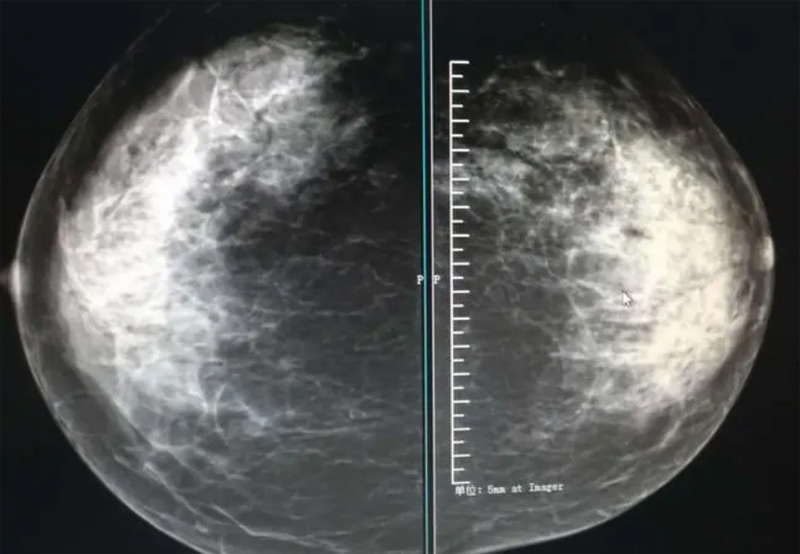

乳腺DR攝影體位有頭尾位及內(nèi)外側(cè)斜位,

乳房在片子的中央,乳頭切線位,可見小部分胸大肌,內(nèi)側(cè)乳腺組織應全部包括在片中,外側(cè)乳腺組織盡可能包括在片中。一張好的MLO位圖像顯示如下:乳房被推向前上,乳腺實質(zhì)充分展開,胸大肌可見,較松弛,下緣達到乳頭水平,乳頭在切線位,部分腹壁包括在片中,但與下部乳腺分開,絕大部分乳腺實質(zhì)顯示在片中。乳腺組織外緣可見乳頭的輪廓;乳腺后方的脂肪組織被很好地顯示出來,乳房無皺褶。對于CC位及MLO位顯示不良或未包全的乳腺實質(zhì),可以根據(jù)病灶位置的不同選擇以下體位:外內(nèi)側(cè)位(LM)、內(nèi)外側(cè)位(ML)、內(nèi)側(cè)頭尾軸位(MCC)、外側(cè)頭尾軸位(LCC),尾葉位(CLEO)及乳溝位。在臨床實踐中,對于常規(guī)體位上發(fā)現(xiàn)的異常改變,可以進一步采取一些特殊的攝影技術,包括局部加壓攝影、放大攝影或局部加壓放大攝影技術。

2、規(guī)范觀圖程序:屏幕軟閱讀或在專用日光觀片燈下膠片閱讀,后者應同時準備白熾強光燈及觀片放大鏡。注意雙側(cè)乳腺配對觀察,推薦雙眼橫向掃描,進行雙乳相同部位圖像比較分析。

3、乳腺實質(zhì)背景的確定:觀察乳腺實質(zhì)與脂肪的構成比例,了解乳腺實質(zhì)類型,以判斷對某些乳腺攝影征象敏感性的影響,有利于確定乳腺攝影對疾病的診斷價值。

必須指出的是,美國放射學會提出的乳腺影像報告和數(shù)據(jù)系統(tǒng)(Breast Imaging Reporting and Data System, BI-RADS)將乳腺分為4型:脂肪型(乳腺內(nèi)幾乎全部為脂肪組織,腺體組織占25%以下)、少量腺體型(乳腺內(nèi)散在腺體組織,大約占25%~50%)、多量腺體型(乳腺呈不均勻致密表現(xiàn),腺體組織大約占51%~75%)、致密型(乳腺組織非常致密,腺體組織占75%以上)。這種分型的主要意義在于說明X線對不同乳腺類型中病變檢出的敏感性不同,對發(fā)生在脂肪型乳腺中病變的檢出率很高,而對發(fā)生在致密型乳腺中病變的檢出率則有所降低,臨床醫(yī)師了解這一點很重要。